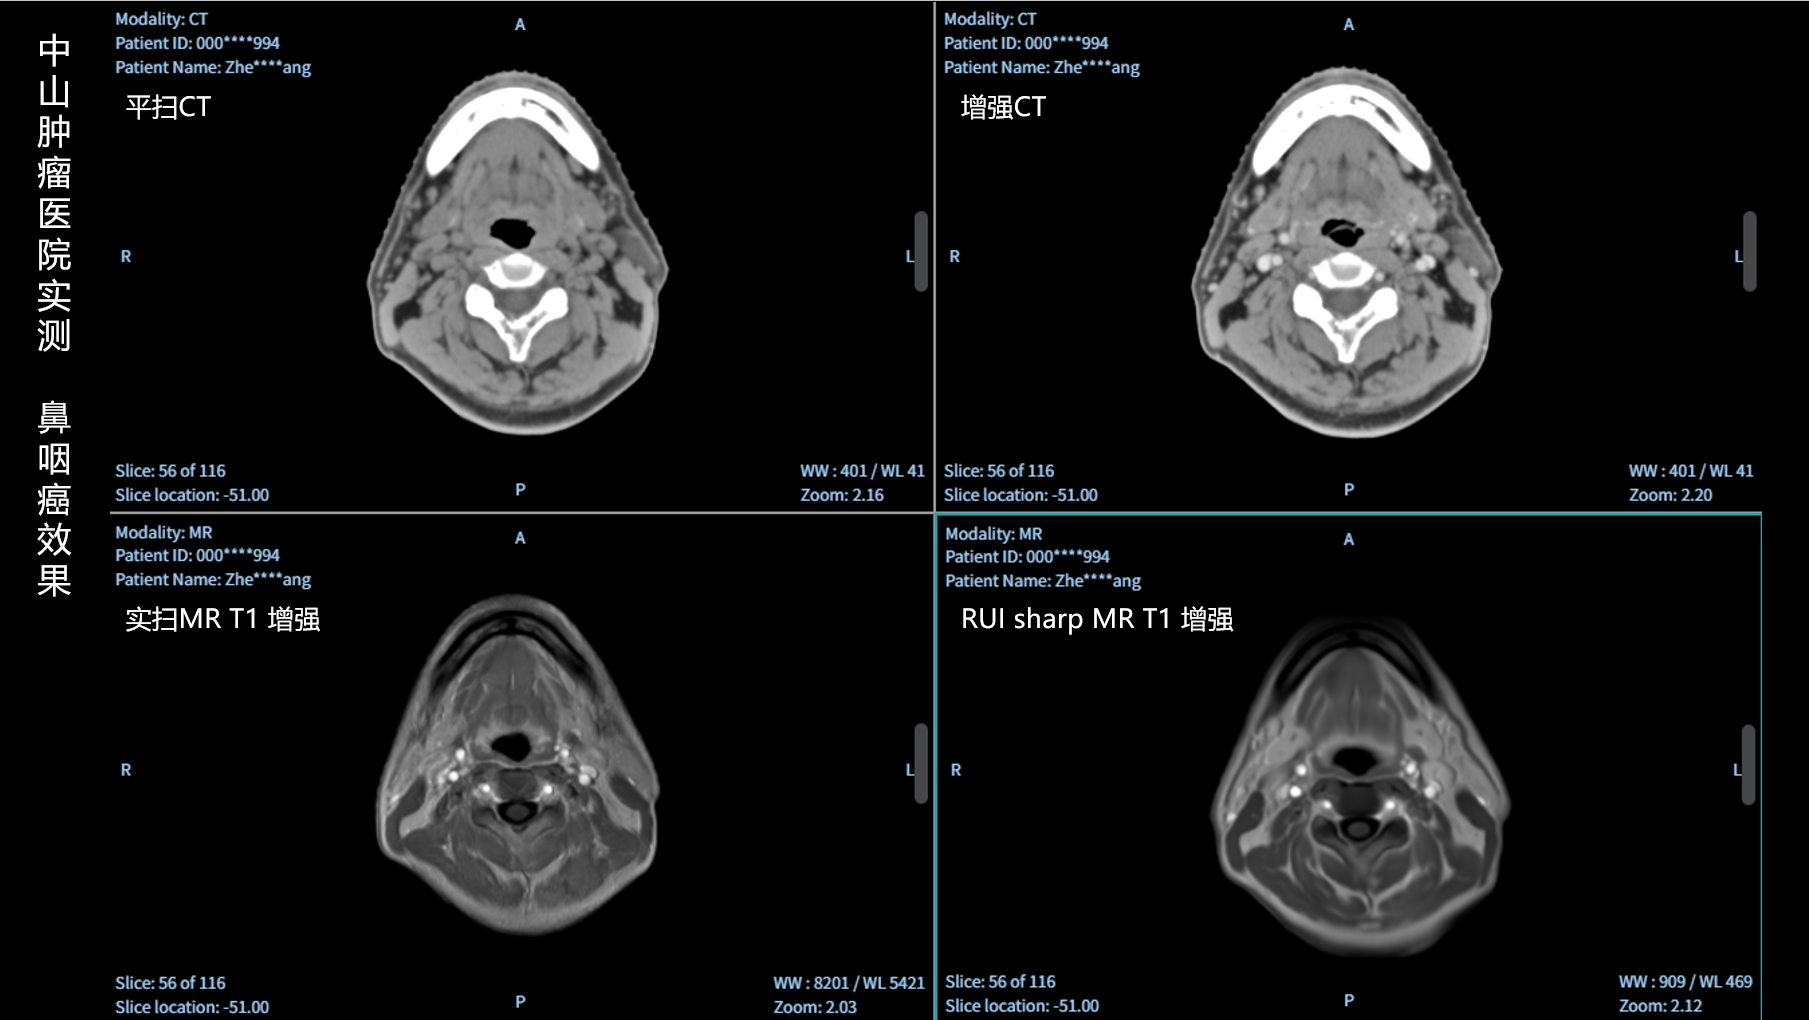

RUI sharp H(锐影)可在不依赖MRI的前提下,显著提升头部CT图像的软组织分辨率,为临床提供更高质量的辅助信息,尤其适用于MRI资源受限或较难配准的头颈部放疗感兴趣区勾画场景。

可大幅提高头部CT影像软组织分辨率,使肿瘤和周边器官显示更清晰,为放疗靶区勾画提供参考。

无需图像配准,CT和锐影图像同源,可匹配、叠加、"淡入淡出"显示。